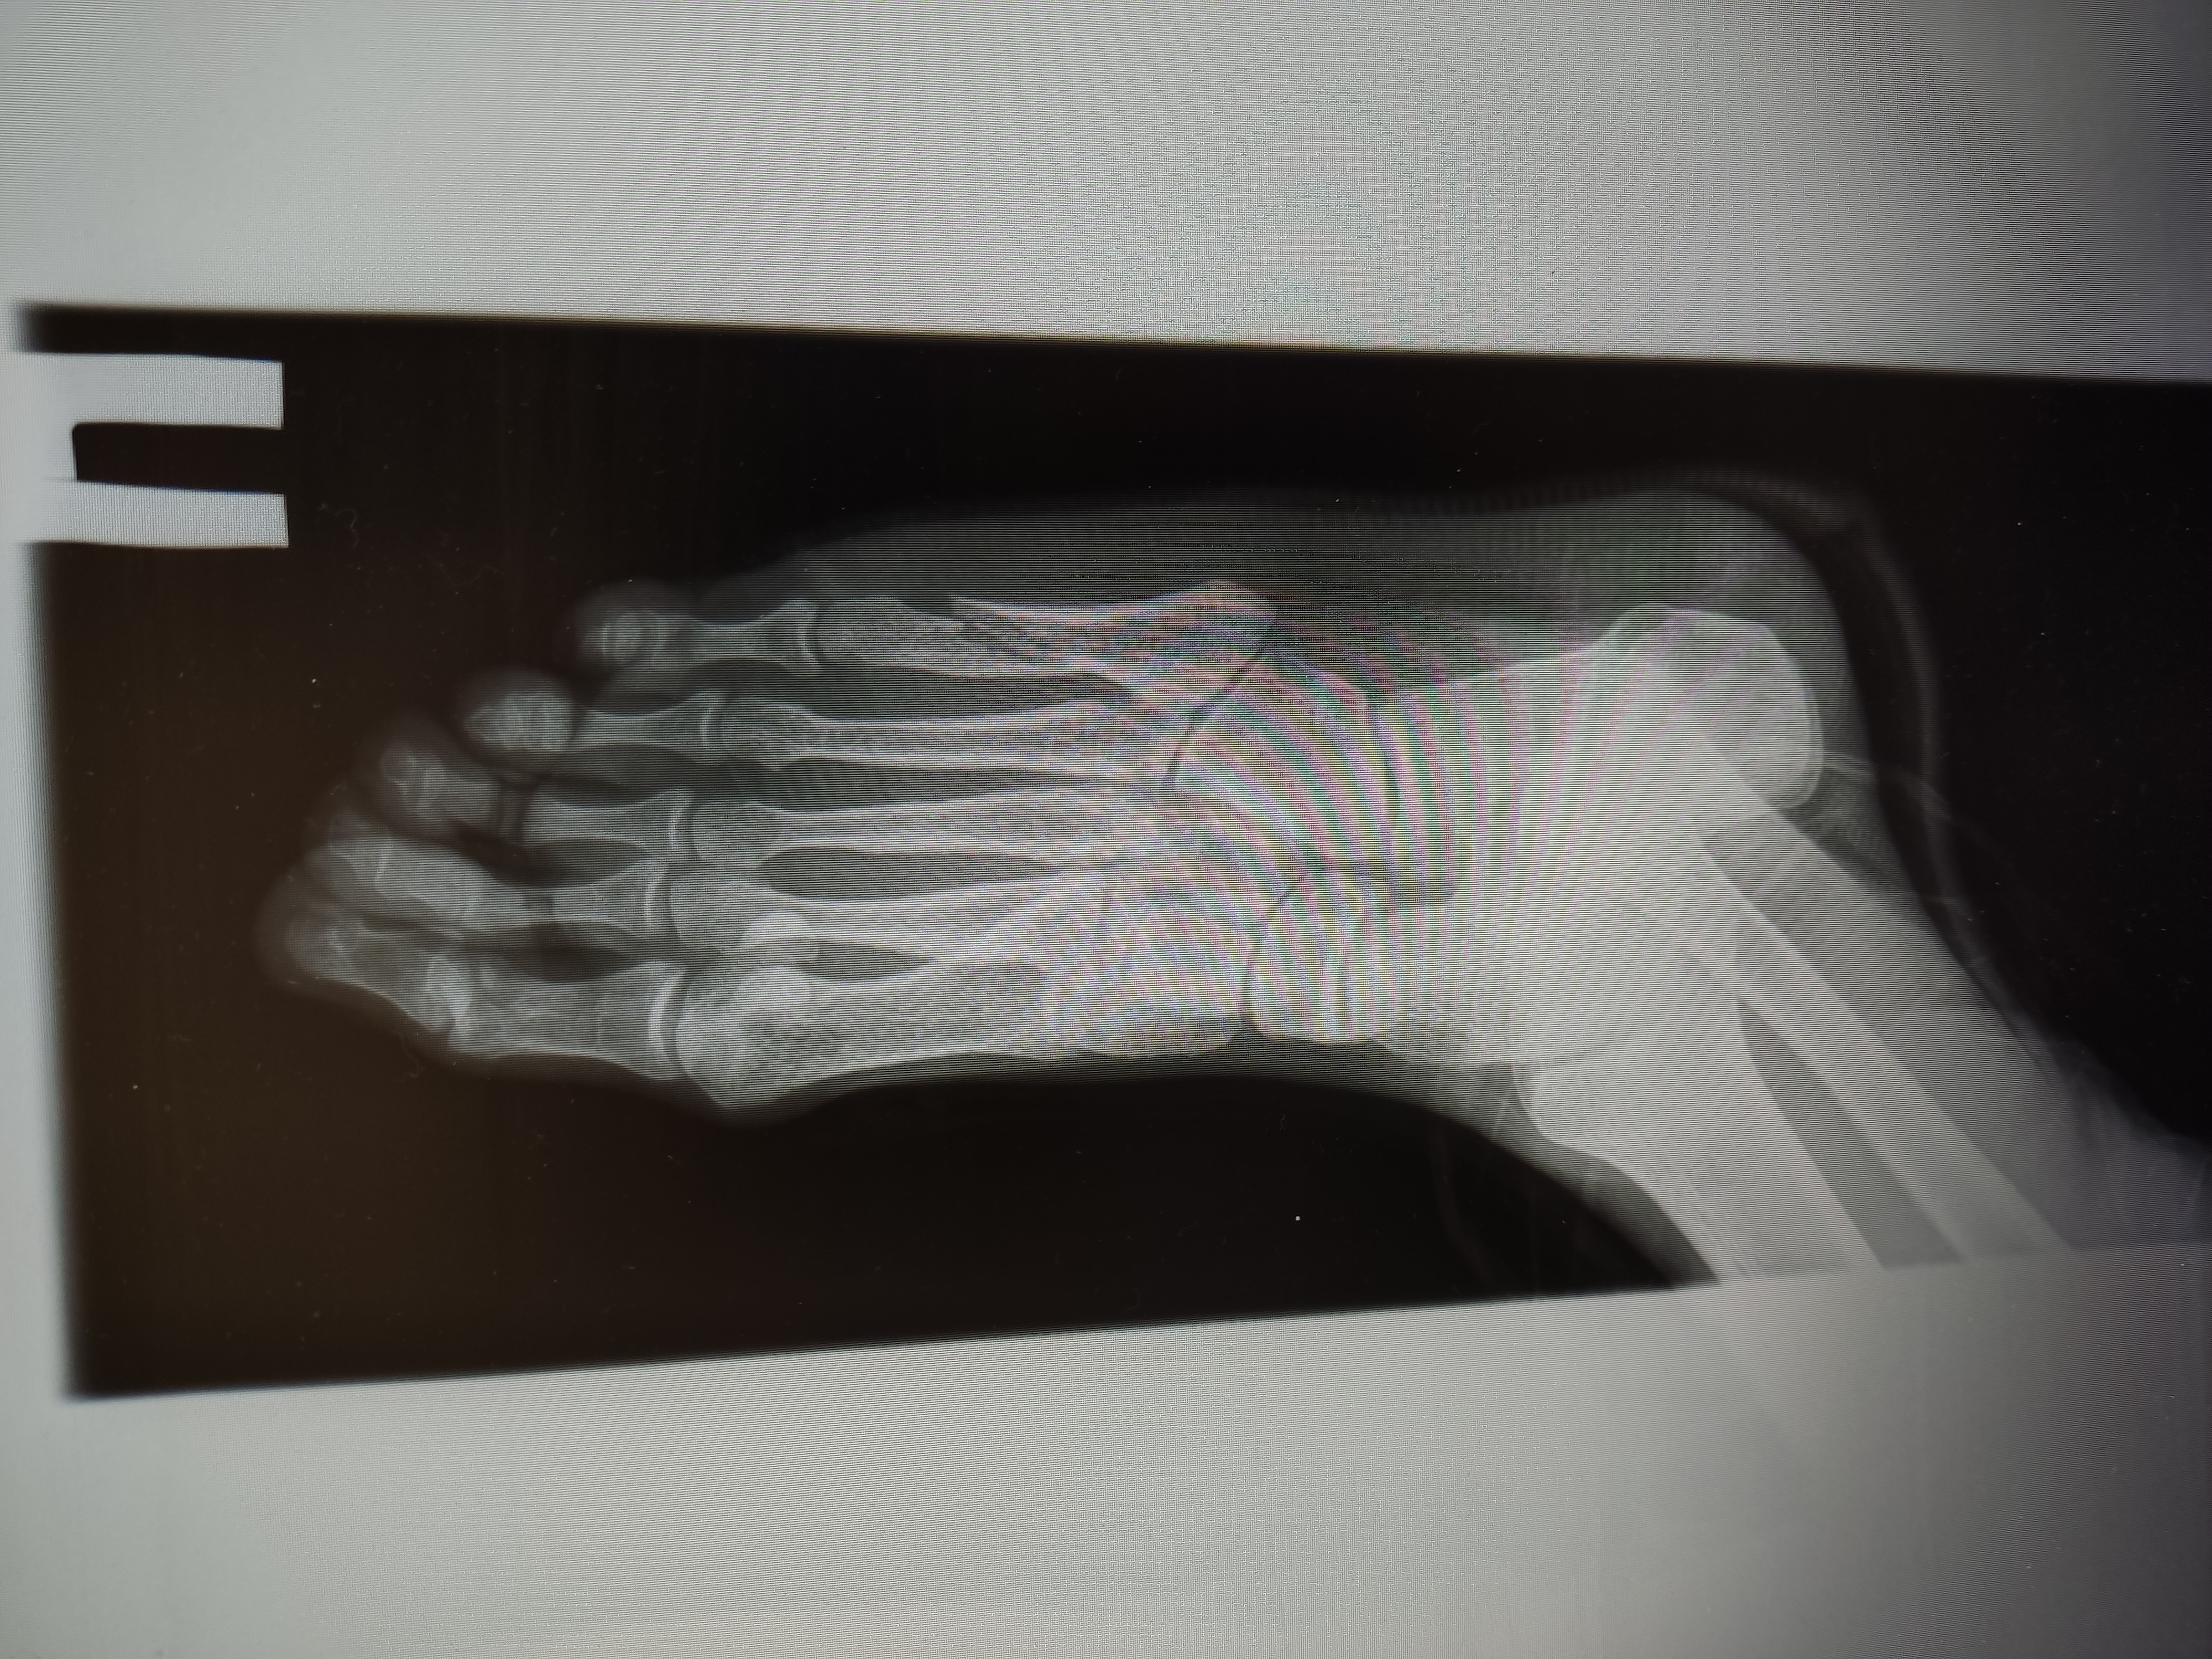

Анончики, не знаю в какой тред пойти, спрошу тут

На пикрил снимок спустя 14 дней после травмы.

Перелом пятой плюсневой со смешением 4мм, произошёл когда подвернул ногу, 32лвл

Гипс наложил на следующий день после травмы в травматологии травму получил в чужом городе.

Операцию не делали и ни один из двух травматологов моего и не моего города не говорил о её необходимости

Сейчас прошло 4 недели с травмы, местный врач сказала снимать гипс, врач другого города изначально говорил про 6 недель в гипсе. Назначили физио, скорее всего алмаг, точно узнаю на процедуре в понедельник

Основной вопрос — какова вероятность того, что я всю оставшуюся жизнь буду хромать?

>>1651107

Гипс сняли на 4 неделю писал прошлый пост без гипса уже, в день его снятия

Вчерашние снимки выглядят так, тут уже 5 недель с момента перелома

>переломы 1 и 5 плюсневых костей оперируют

Ну вот мне ни один из двух врачей не предлагал

>пей витаминку Д и какой нибудь кальций (кальцемин или остеогенон)

КальцД3 никомед и остеогенон начал пить на 3-4 день после перелома и пью до сих пор